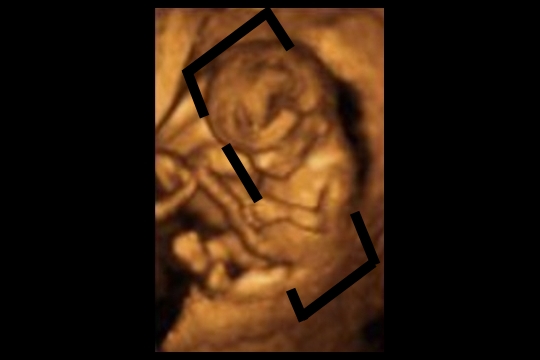

Corte coronal